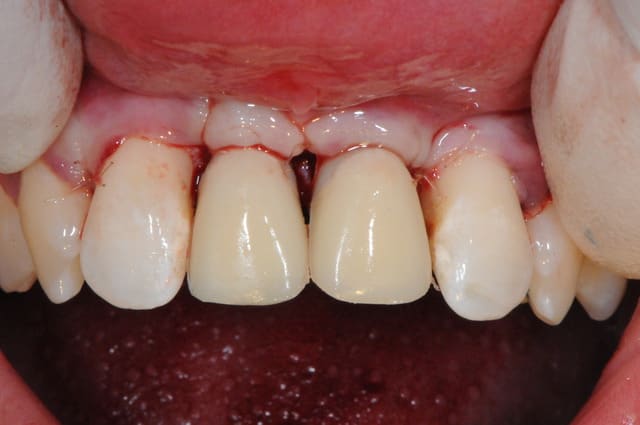

C'est un très joli travail tout d'abord, mais ton frein ne risque-t-il pas de gêner, si oui, tu comptes faire la chir mucco après ?

PS : l'angle de la photo est peut-être trompeur...

Sinon, c'est normal d'avoir plusieurs spires à nu sur l'implant remplaçant la 11 ?

J'ai bien peur que tu aies massacré tes papilles aussi bien dent/implant que implant/implant :-(((